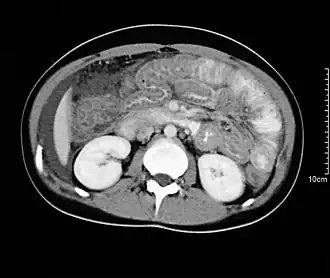

При исследовании печени, поджелудочной железы и жёлчных протоков ведущую роль занимают ультразвуковые исследования (УЗИ), компьютерная томография (КТ) и магнитно-резонансная томография (МРТ). При диагностике состояния пищевода распространено рентгеновское исследование с барием, при котором прохождение глотков бариевой взвеси регистрируется флюороскопически в реальном масштабе времени. Рентгенография пищевода применяется для выявления грыж пищеводного отверстия диафрагмы, опухолей, дивертикулов, стриктур, варикозного расширения вен, инородных тел. Рентгенография или рентгеноскопия с двойным контрастированием или без него применяется при исследовании желудка и двенадцатиперстной кишки с целью выявления язв, опухолей, стриктур, обтураций, контроля результатов оперативных вмешательств. Для диагностики опухолей кишечника, воспалительных заболеваний, причин непроходимости кишки, стриктур, обструкции применяется контрастная рентгенография, компьютерная или магнито-резонансная томография[28].

МРТ-изображение содержащих камни жёлчного пузыря и протоков